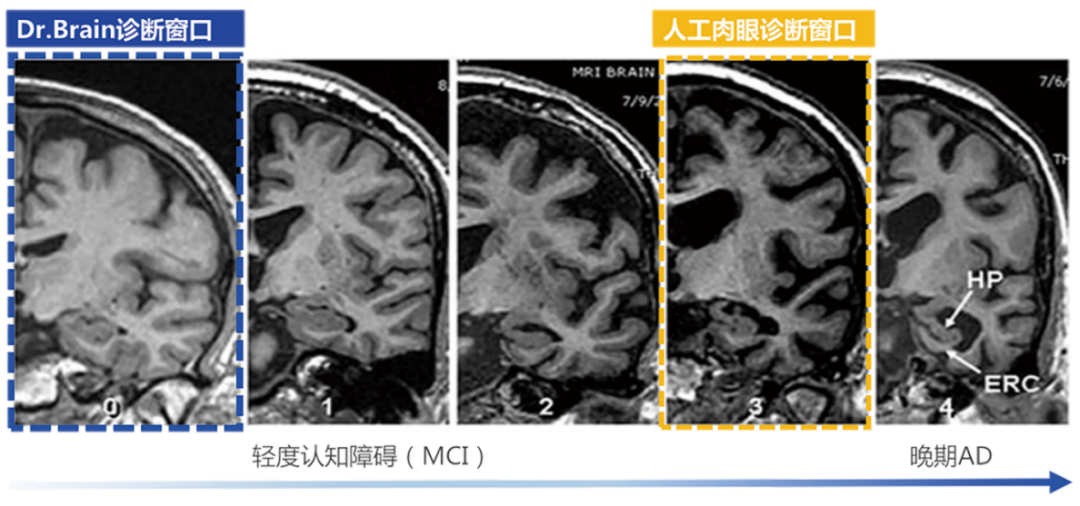

破解AD的關(guān)鍵——在于早發(fā)現(xiàn)、早診斷、早治療

針對AD的治療,國際上已批準(zhǔn)的AD藥物基本都是對早期AD患者在延緩病程發(fā)展上有顯著療效,但對于晚期患者,即使檢出也是療效甚微?!栋柎暮D?chuàng)新藥物臨床試驗中國專家共識》強(qiáng)調(diào)AD應(yīng)著力于早期發(fā)現(xiàn)和預(yù)防,而臨床現(xiàn)狀是AD的診斷率低且漏診率高。因此,AD的早篩、早診對延緩該疾病的發(fā)展至關(guān)重要。臨床中對AD診斷首選的影像學(xué)檢查方法是磁共振成像 (Magnetic Resonance ImagingMRI) ,但臨床上大多數(shù)醫(yī)生認(rèn)為AD病人的腦結(jié)構(gòu)異常變化發(fā)生較晚,而今借助AI算法,其實醫(yī)生能在高維空間捕捉到宏觀和微觀、具體和抽象的腦結(jié)構(gòu)特征,可以輔助醫(yī)生利用MRI結(jié)構(gòu)影像在早期精準(zhǔn)診斷AD性質(zhì)的腦結(jié)構(gòu)異常改變。因此,人工智能應(yīng)用于影像診斷和疾病篩查診斷近年來變?yōu)槿蜥t(yī)療器械業(yè)界的趨勢與熱點,其中,在腦部疾病診療領(lǐng)域,即有可能改變將來的AD診療路徑。

超早期的診斷

利用AI算法識別肉眼難以發(fā)現(xiàn)的腦結(jié)構(gòu)超早期的細(xì)微改變,大幅提前疾病診斷窗口